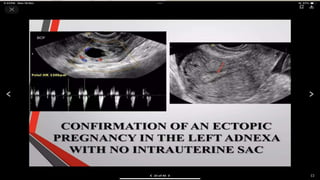

Ectopic pregnancy types and radiology us findings

Ectopic Pregnancy Types And Radiology Us Findings | PPT

ectopic pregnancy types and radiology us findings | PPT www.slideshare.net